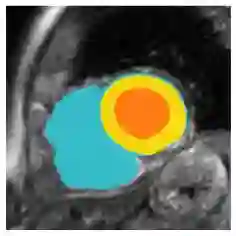

Although supervised deep-learning has achieved promising performance in medical image segmentation, many methods cannot generalize well on unseen data, limiting their real-world applicability. To address this problem, we propose a deep learning-based Bayesian framework, which jointly models image and label statistics, utilizing the domain-irrelevant contour of a medical image for segmentation. Specifically, we first decompose an image into components of contour and basis. Then, we model the expected label as a variable only related to the contour. Finally, we develop a variational Bayesian framework to infer the posterior distributions of these variables, including the contour, the basis, and the label. The framework is implemented with neural networks, thus is referred to as deep Bayesian segmentation. Results on the task of cross-sequence cardiac MRI segmentation show that our method set a new state of the art for model generalizability. Particularly, the BayeSeg model trained with LGE MRI generalized well on T2 images and outperformed other models with great margins, i.e., over 0.47 in terms of average Dice. Our code is available at https://zmiclab.github.io/projects.html.

翻译:虽然监督的深层学习在医学图像分割方面取得了有希望的成绩,但许多方法无法在隐蔽数据上一概而论,限制了其真实世界的适用性。为了解决这一问题,我们提议了一个深层次的学习基础巴伊西亚框架,这个框架共同模拟贝伊西亚图像和标签统计,利用与领域相关的医学图像的轮廓进行分解。具体地说,我们首先将图像分解成轮廓和基础的构件。然后,我们将预期的标签作为仅与轮廓有关的变量进行模拟。最后,我们开发了一个变异的巴伊西亚框架,以推断这些变量的后端分布,包括轮廓、基础和标签。这个框架是用神经网络共同实施的,因此被称为深巴伊西亚分解。关于交叉序列心脏分解任务的结果显示,我们的方法为模型的可通用性设定了一个新的状态。特别是,与LGE MRI 培训的ByeSege模型在T2图像上普遍普及,并优于大边距的其他模型,即0.47以上为平均的Dimicus/ https.